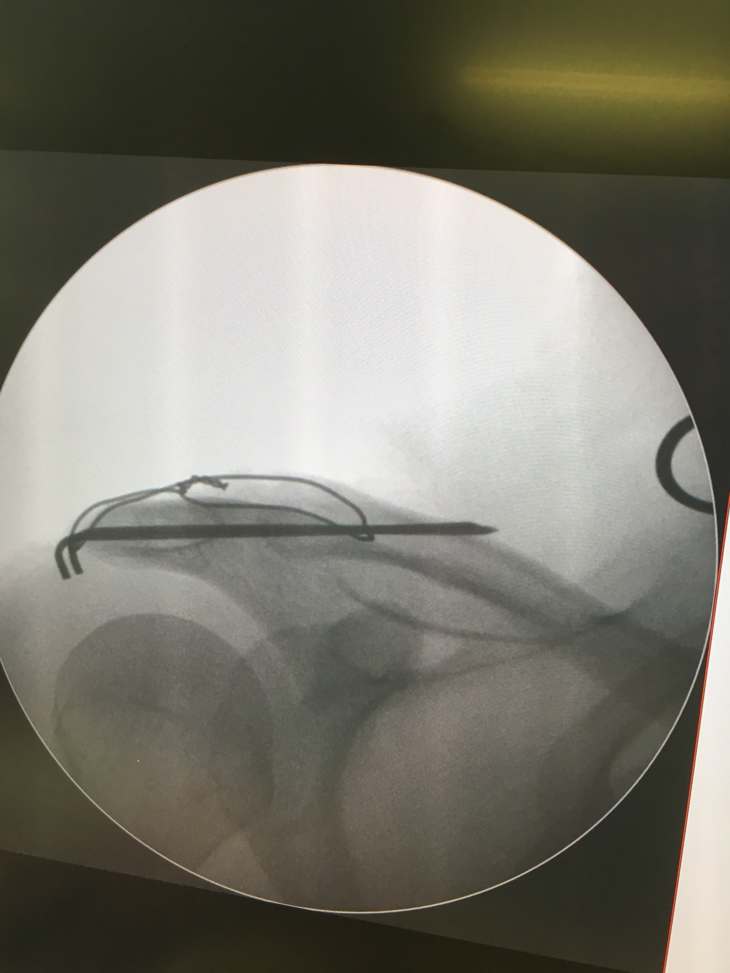

Začátek sezóny a tak blbě mě ztrestal pumptrack. No to nasere, čekal jsem že to bude „jen“ vyhozené rameno, no když mi řekli že to bude na operaci a drátování, moc mě nepotěšili. Snad to bude mít rozumný průběh, ať ještě cosi stihnu letos…

No kdyby aspoň na konci…dnes 4. den po operaci, v pohodě nebolí, jen tlačí dráty když ležím, ale 6 týdnů ortéza a pak rehabky. Tak sám sem zvědavý jak to pude…